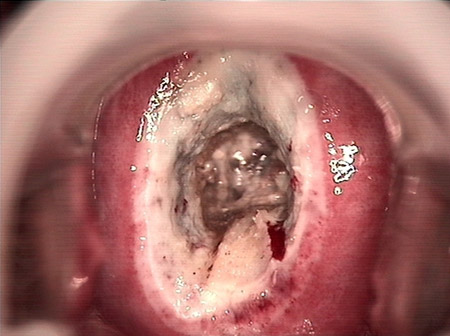

婦科leep錐切手術 CIN2-3

• CIN 2-3CIN 2-3